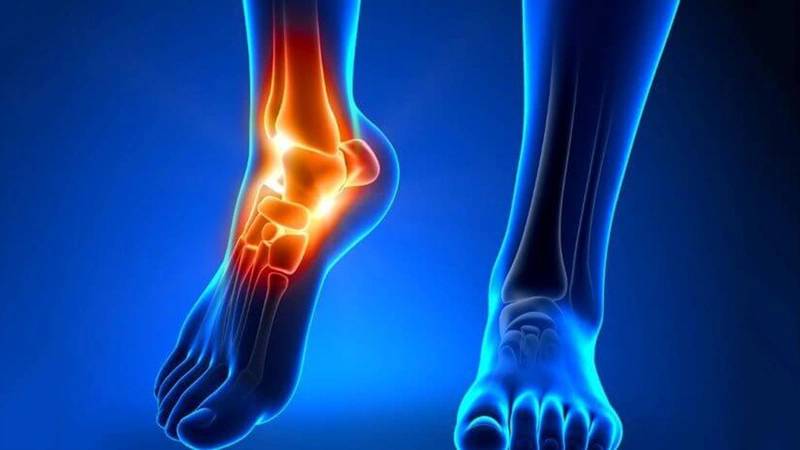

Xương thuyền phụ là một phần xương hoặc mảnh sụn phụ nằm bên trong của bàn chân, ở gần vùng vòm gan chân. Nó có thể nằm riêng lẻ hoặc gắn liền với gân chày sau, là gân mà gắn vào xương thuyền. Hãy tìm hiểu chi tiết về hội chứng xương thuyền phụ và cách điều trị cùng với Nhà Thuốc Long Châu.

Xương thuyền phụ là một loại dị tật bẩm sinh ở lòng bàn chân, khiến cấu trúc xương bên trong chân có một mảnh sụn bổ sung hoặc xương phụ ở phía trên vòm gan chân. Thường thì, xương thuyền phụ không được phát hiện cho đến khi xương và sụn phát triển (trong giai đoạn thanh thiếu niên) hoặc trưởng thành.

Đây là một loại xương phụ trong bàn chân, xuất phát từ sự phát triển không bình thường, dẫn đến sự phì đại về phía trong và gan chân của xương thuyền. Xương thuyền phụ tồn tại như một xương nhỏ nằm trong gân chày sau và liên kết với xương thuyền hoặc đôi khi cũng gắn liền với xương thuyền.